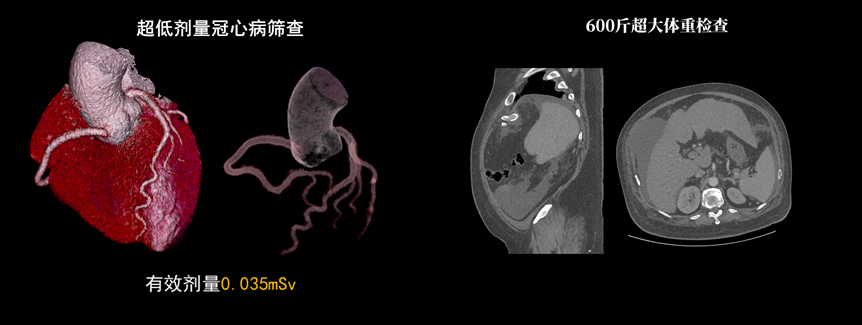

液態(tài)金屬軸承球管,陽極直冷技術(shù),提供30MHU球管熱容量,可高通量連續(xù)掃描。AI劑量調(diào)制、迭代重建等復(fù)合劑量控制方案,為體檢患者提供優(yōu)化劑量掃查。82cm大孔徑,讓大體型患者檢查更加舒適。

天河640CT的寬體探測器單圈掃描即可覆蓋全心臟,搭配快速機(jī)架轉(zhuǎn)速和獨家AI冠脈追焦技術(shù),可實現(xiàn)單心動周期內(nèi)無限心率、無限心律的冠脈成像,對于嚴(yán)重心律不齊、房顫、房撲,超高心率等情況,天河640CT都能在單心動周期內(nèi)獲得優(yōu)質(zhì)圖像。